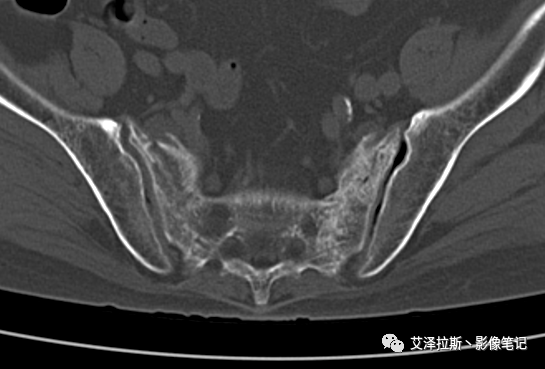

病例2:患者,女性,69岁,老年性骨质疏松症。

CT平扫:

X线、CT:骶骨重度骨质疏松,双侧骶骨翼皮质断裂,分别见迂曲走行的纵行透亮线位于骶孔外侧,大致与骶髂关节间隙平行,骨折端局部可见骨痂、骨质硬化。

骶骨功能不全骨折

①单侧或者双侧骶骨翼骨折,典型者呈“H”形,即“Honda征”;

②骨折线位于骶孔外侧(如下图,主要发生于1区),通常可能会伴随耻骨的功能不全骨折(如:病例2 右侧耻骨上支骨折,L5双侧横突骨折);

③愈合期骨折线模糊,骨痂形成,骨质硬化;